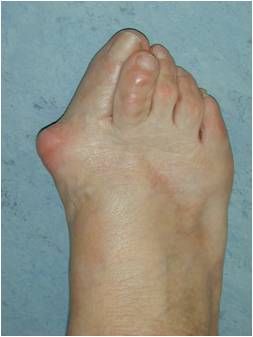

A bunion / Hallux Valgus is term for a boney bump that has formed on the inner aspect of the forefoot at the main big toe joint (Fig 1).

The medical term is hallux valgus, hallux being the latin name for the big toe, valgus describing the leaning of the big toe away from the midline of the body. This condition can run in families, presenting as early as adolescence or be acquired in later life (eg. as a result of footwear).

Symptoms include pain in the bump area with or without shoes and occasionally associated discomfort in the ball of the foot (metatarsalgia) and/or lesser toe deformities (Fig 2) such as a hammertoe from direct pressure of the big toe. The diagnosis is confirmed by clinical assessment and x-rays (Fig 3).